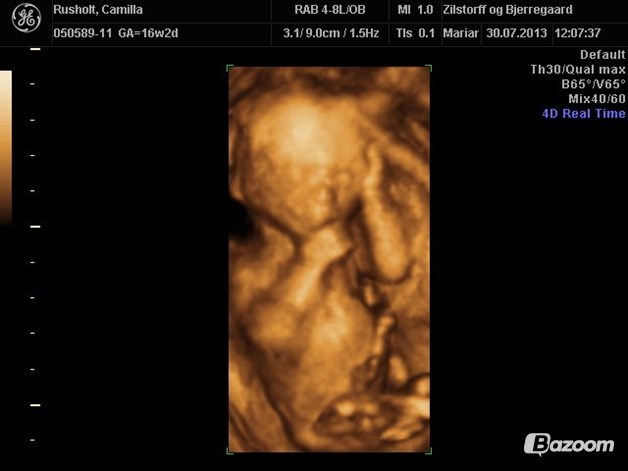

**Ønskebabyen

Vi var til kønsscanning i uge 16, hvori der også var lidt 3D

Vedhæftede fotos (klik for at se i fuld størrelse)